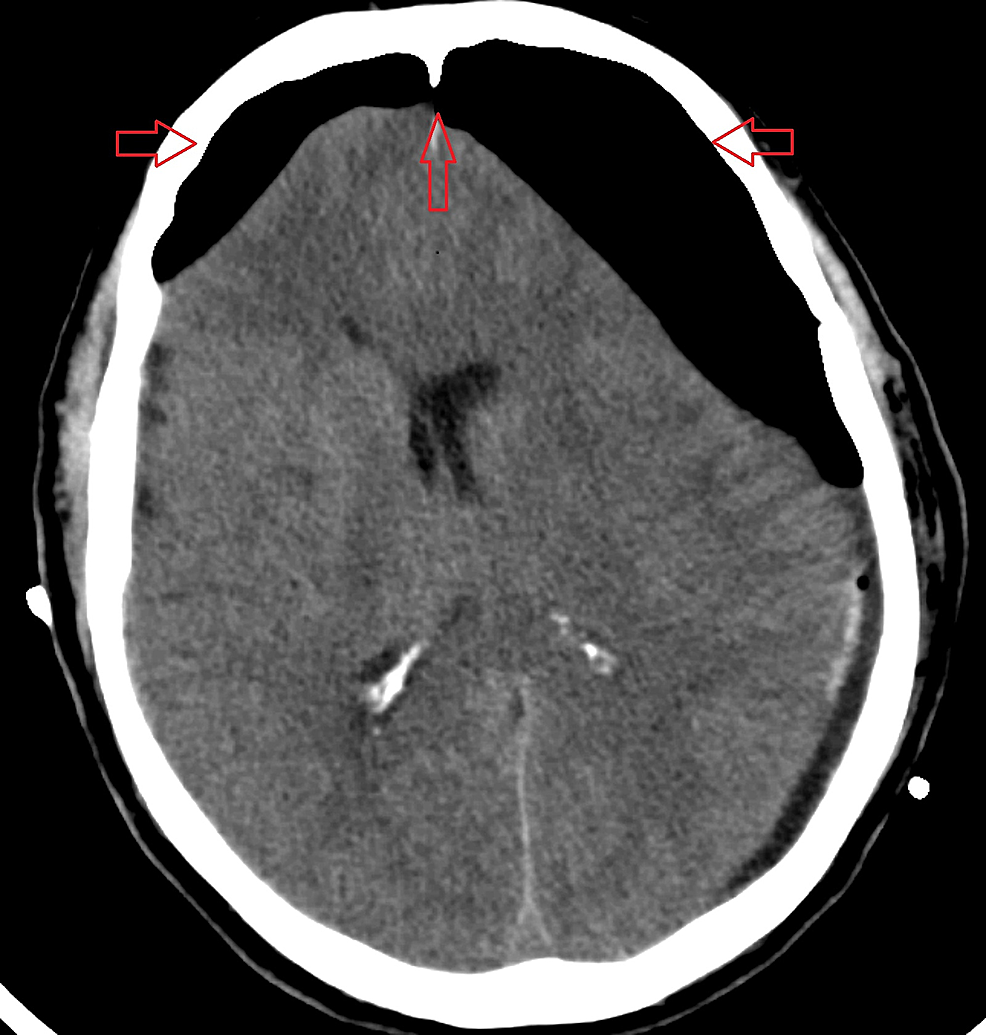

Mount Fuji Sign Radiology Reference Article Radiopaedia Org

radiopaedia.org

Mount Fuji Sign Is Seen On Cross Sectional Imaging And Implies Tension Pneumocephalus Is Present The Sign Refers To The Pres Radiology Frontal Lobe Vp Shunt